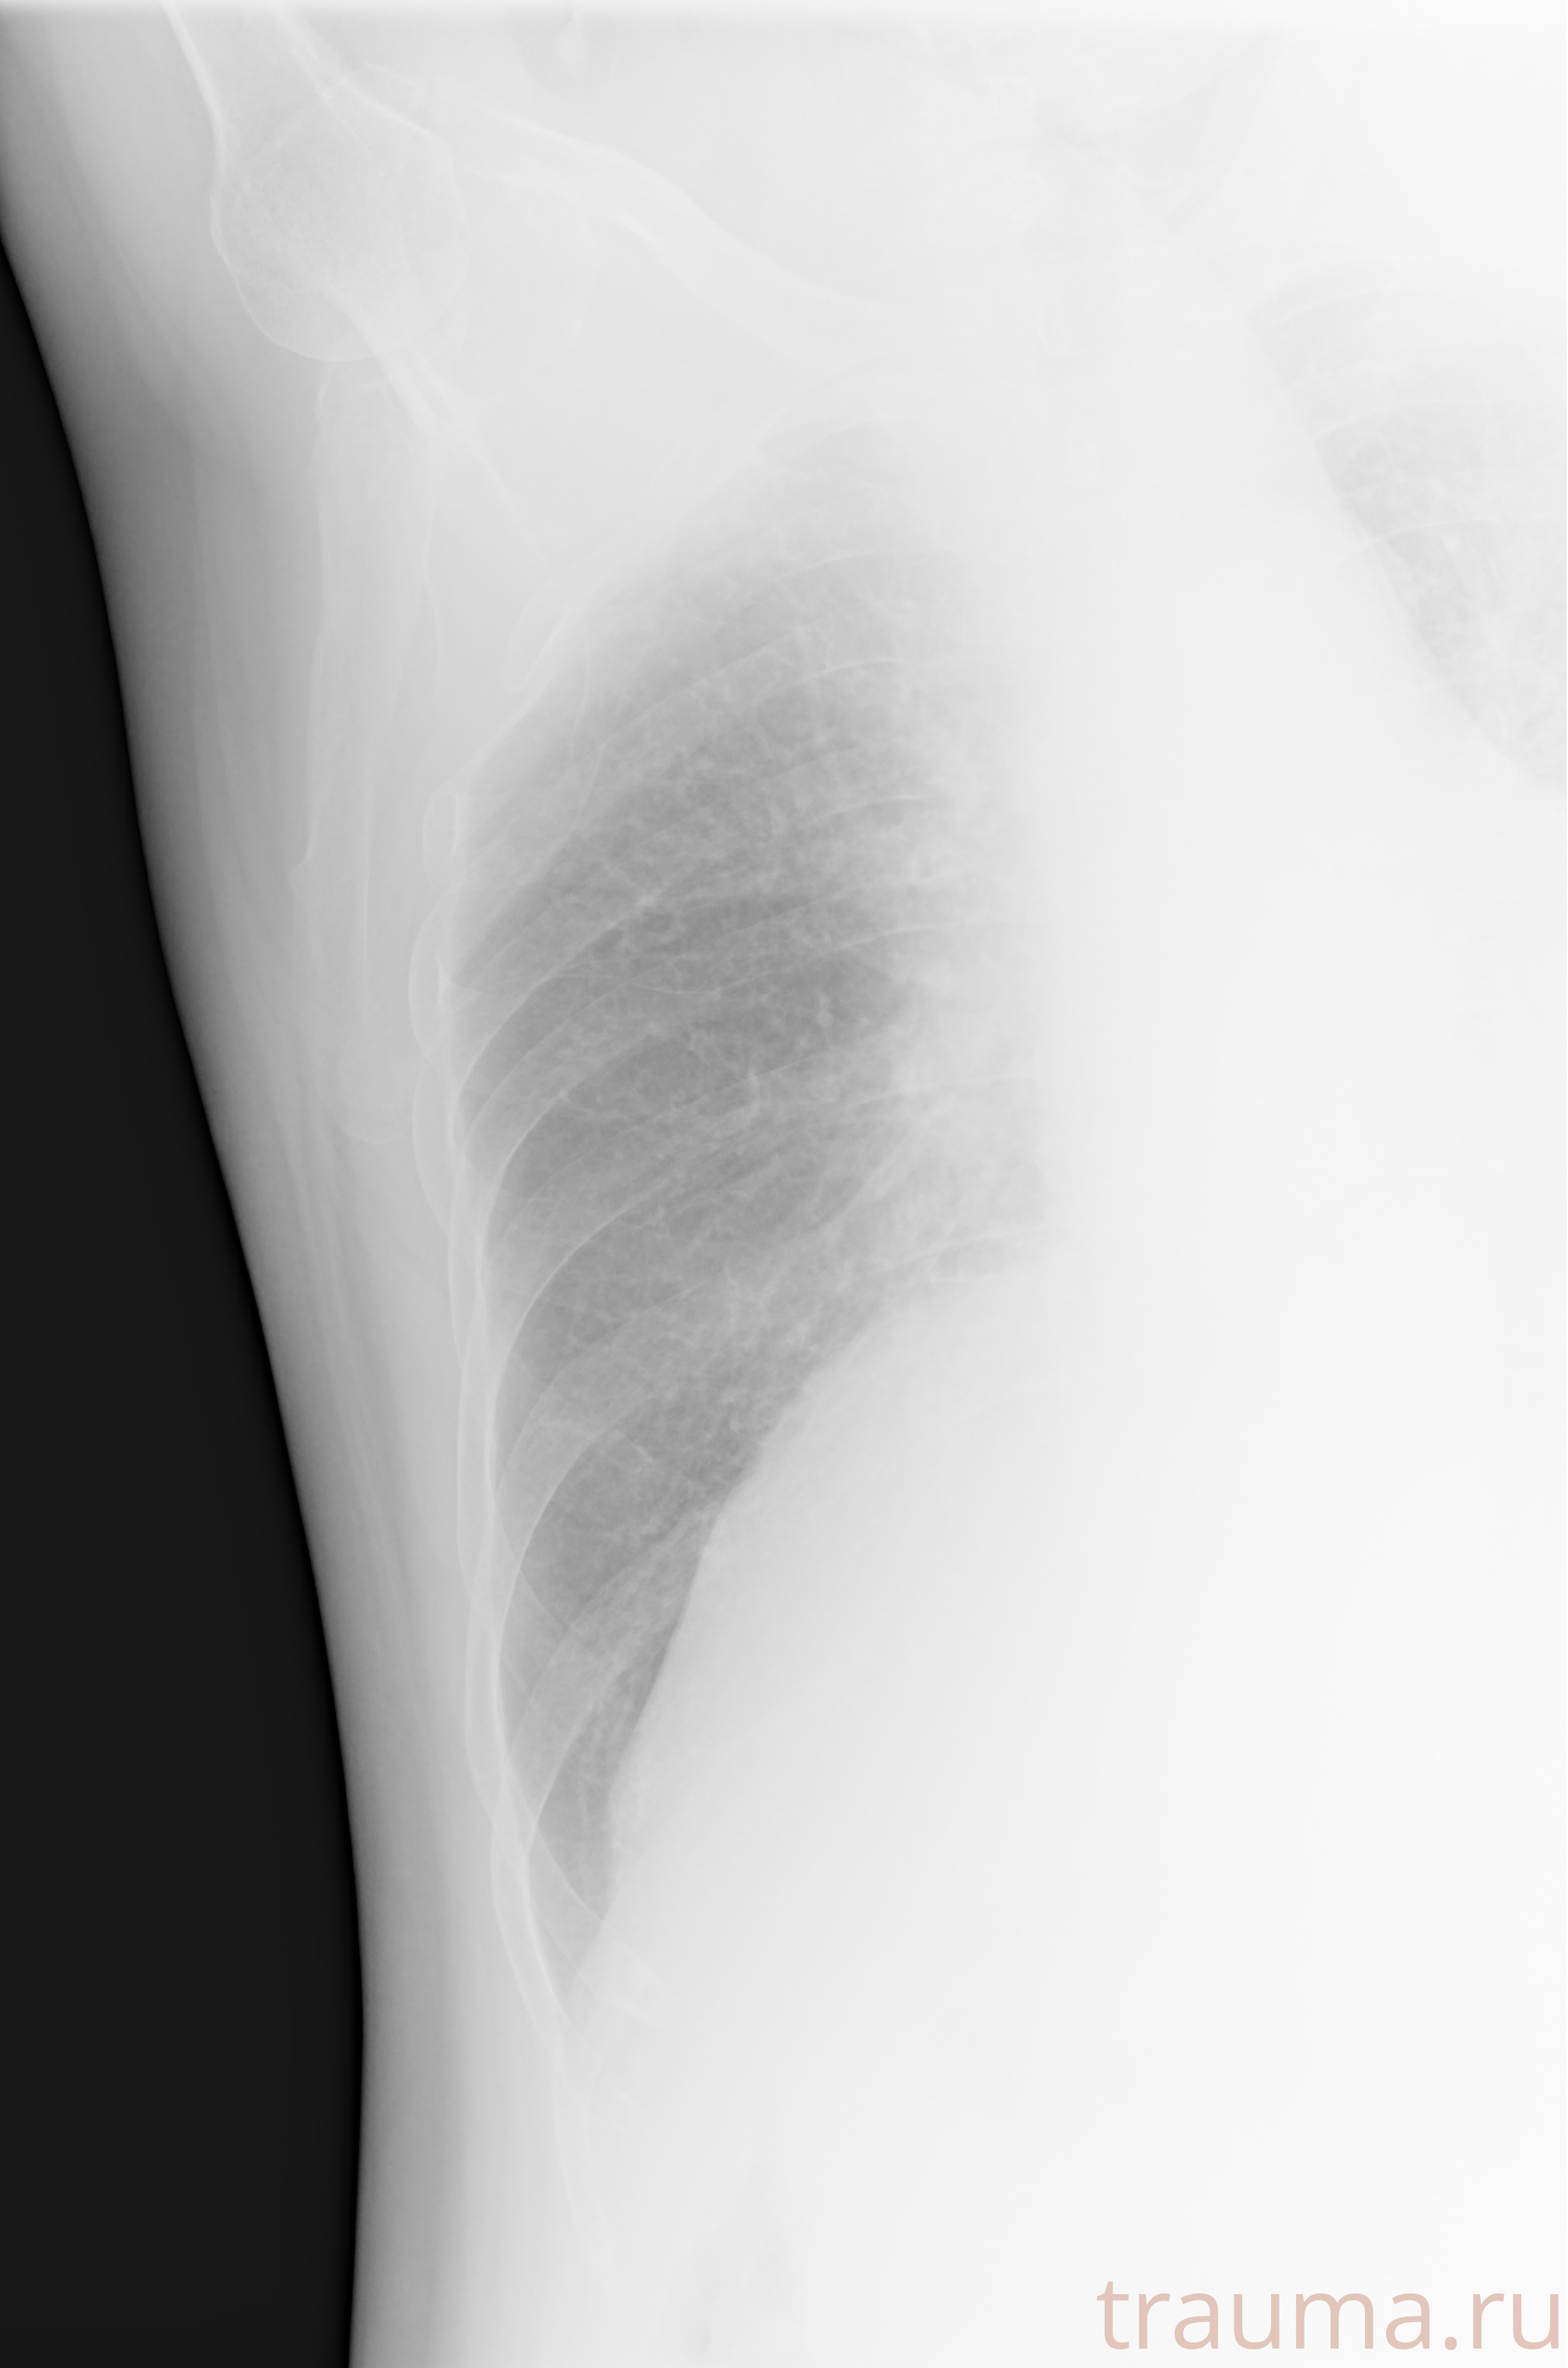

Рентгенограммы

Рентген на дому: по вашему адресу приезжает врач-рентгенолог, травматолог-ортопед с мобильным рентгеновским аппаратом, проводит диагностику травмы или заболевания, делает необходимые рентгенограммы, дает рекомендации по дальнейшему лечению. Получить качественные снимки в домашних условиях возможно благодаря уникальной методике, разработанной МосРентген Центром для института  Склифосовского

при переломе шейки бедра и пневмонии от компании МосРентген Центр - партнера Института имени Склифосовского